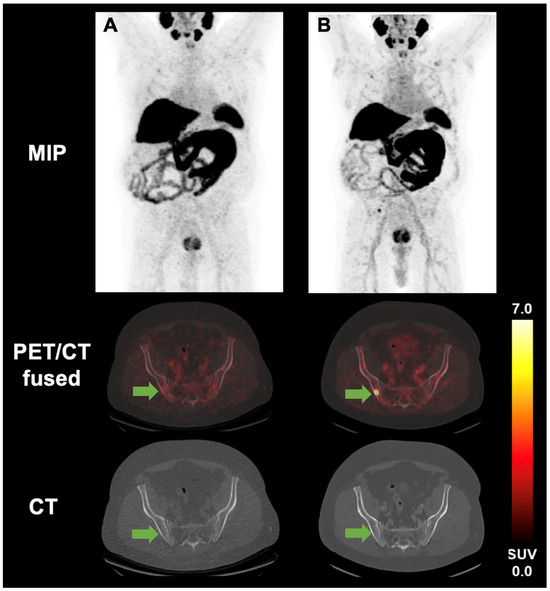

3.2. Image Analysis